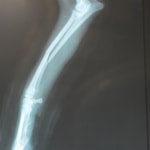

トイプードル 右遠位橈尺骨短斜骨折のALPSによる内固定